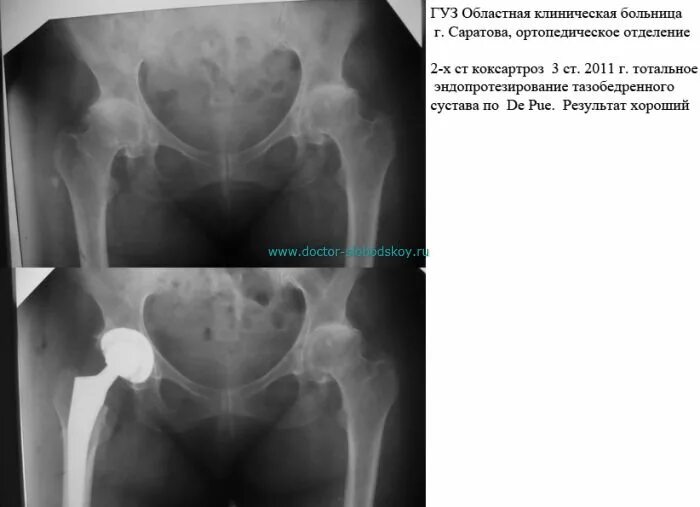

Коксартроз тазобедренного инвалидность положена